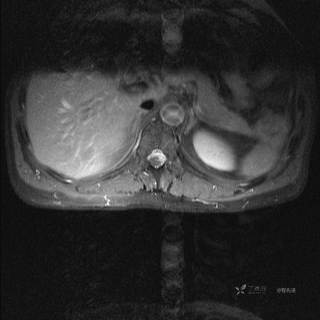

MR

T2

T2压脂

T1

T1增强

T1增强冠状位

T1增强横断位